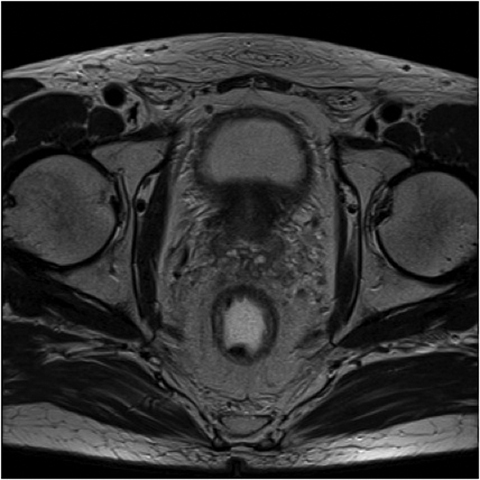

Fig.2. Același pacient post chimio-/ radioterapie – răspuns complet cu dispariția masei tumorale rectale; dispariția restricției de difuzie și reducere în dimensiuni a ganglionilor mezorectali; pacientul a beneficiat de TME şi s-a confirmat histopatologic absenţa ţesutului tumoral (pT0 pN0).

a-d) imagini T2 ponderate în 3 planuri

e) difuzie RM (b1000)

f) sagital T1 postcontrast